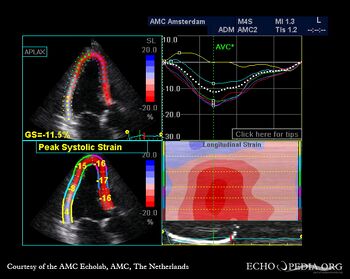

A3CH: akinesia of basal posterior wall A4CH: strain image

E00522.jpg

E00523.jpg

A2CH: strain image A3CH: strain image